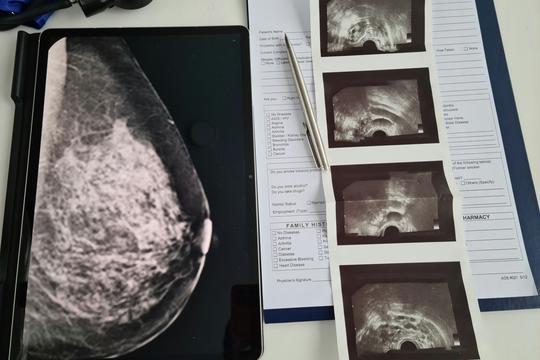

Mamografija uz pomoć AI-a može predvidjeti 5-godišnji rizik od raka. Evo što mame trebaju znati

Foto: Unsplash+

Zamislite da jedan običan mamograf ne pokazuje samo je li sve trenutno u redu, već vam može reći i koliki je vaš rizik za rak dojke u idućih pet godina. Zvuči pomalo zastrašujuće, ali i ohrabrujuće. Nova AI tehnologija upravo to omogućava, a za mnoge mame to bi mogla biti prekretnica u brizi za vlastito zdravlje.

Nova generacija alata za očitavanje mamografije, potpomognuta umjetnom inteligencijom, tiho ulazi u ordinacije i mogla bi promijeniti način na koji mame razmišljaju o preventivnim pregledima.

Jedan od takvih alata, Clairity, već je dobio odobrenje američke agencije FDA i koristi AI za procjenu rizika od raka dojke do pet godina unaprijed, puno ranije nego što se bolest može otkriti klasičnim pregledima ili simptomima.